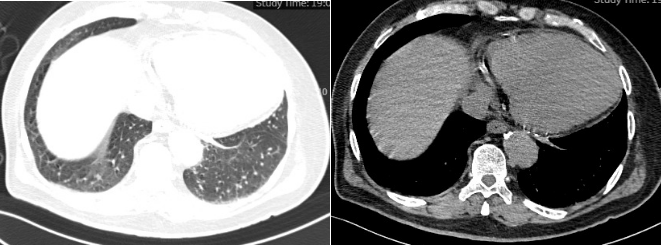

4月29日复查胸部CT如图2所示。

2 复查胸部CT2025-04-29)